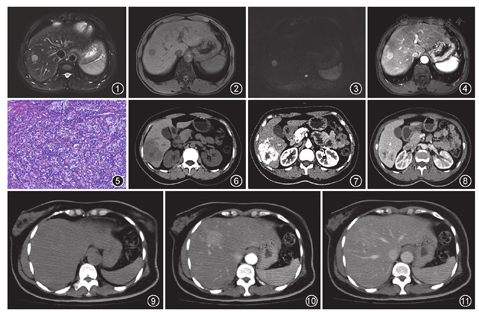

例1男,65岁。剑突下钝痛5个月,外院CT检查提示肝S8段占位性病变。实验室检查:乙肝表面抗原、e抗原和核心抗体阳性(大三阳),癌胚抗原(CEA)值为10.9 ng/ml(正常参考值为0~5 ng/ml)。MRI检查:肝S8段2.5 cm×1.8 cm结节,边界清楚。T2WI呈稍高信号(图1);T1WI呈低信号(图2);DWI可见扩散受限(图3);动态增强扫描动脉早期强化较明显,静脉期强化程度稍减低,但始终高于周围肝实质,病灶中央可见小索条状、斑点状低强化区(图4)。手术所见:肿物位于S8段,边界清楚,行肝S8段肿物切除术。术后病理:组织中可见大量淋巴细胞、浆细胞浸润,异型大细胞条呈索状或片巢状生长,核空泡状,核分裂象易见(图5)。免疫组织化学:Ki67 40%阳性(+),白细胞共同抗原(LCA)、CD3、CD20、CA153、CD110灶性、CD34血管、CK19部分阳性(+),肝细胞特异性抗原(Hepatocyte)、甲胎蛋白(AFP)、EB病毒原位杂交(EBers)阴性。病理诊断:淋巴上皮瘤样癌(lymphoepithelioma-like carcinoma,LELC),周围肝组织汇管区少许淋巴细胞浸润。

例2女,38岁。超声发现肝内占位性病变1个月。实验室检查:乙肝表面抗原、e抗原和核心抗体阳性(大三阳)。CT检查:平扫肝S6段低密度肿块,CT值为37 HU,边界尚清,呈浅分叶状,病灶内可见不规则更低密度多发囊变及坏死区(图6);增强扫描可见病灶动脉期明显不均匀强化(图7),门静脉期病灶实性成分和肝实质强化程度相似,病灶内不规则更低密度区始终未见强化(图8)。手术所见:肝S6段可见直径约8 cm灰白色肿物,侵犯肝包膜,行肝S6段切除术。术后病理:肿瘤细胞呈巢状及梁柱状排列,核分裂象可见,并见淋巴细胞、浆细胞浸润。免疫组织化学:CK、波形蛋白、CK19部分细胞、CK8/18和INI-1少许细胞阳性(+),AFP、Hepatocyte阴性,EBers阳性(+)。病理诊断:LELC伴坏死,汇管区可见炎性细胞浸润。

例3女,50岁。体检超声发现肝门区占位性病变1个月。实验室检查未见明显异常。CT检查:平扫可见肝S8段低密度肿块,边界不清,周围可见环形高密度影(图9);增强扫描动脉期可见病灶呈明显不均匀强化(图10),门静脉期病灶内密度稍高于周围肝实质,其内可见斑片状囊变坏死区(图11)。术中所见:S8段质地较硬肿物,行肝S8段切除术。术后病理:肿瘤由分化较好的腺管和灶性片状结构构成,细胞核大、呈空泡状,核分裂象可见,间质见大量浆细胞浸润,淋巴滤泡增生。免疫组织化学:CK7、CEA、CK19、CK8/18阳性(+),Hepatocyte阴性,CD21、CD23、CD3和CD20显示增生的淋巴组织B、T细胞分布正常。病理诊断:肝内胆管LELC。

本研究中的3例患者影像上均表现为动脉早期强化,门静脉期(静脉期)强化程度与周围肝实质相似或减低,与其他学者的结果相符[1,5],提示病灶动脉血供较丰富。除例2病灶内可见少许小片状坏死,其余病灶信号及密度较为均匀,考虑其与病灶有大量较为致密的淋巴细胞浸润,肿瘤组织密度较大有关。3例患者增强扫描动脉早期强化明显,需要与肝内血管源性疾病鉴别,例2曾误诊为血管内皮细胞瘤。LELC病灶静脉期廓清均不显著,此特征可与肝细胞癌相鉴别。明确诊断LELC仍需依靠组织病理和免疫组织化学检查。